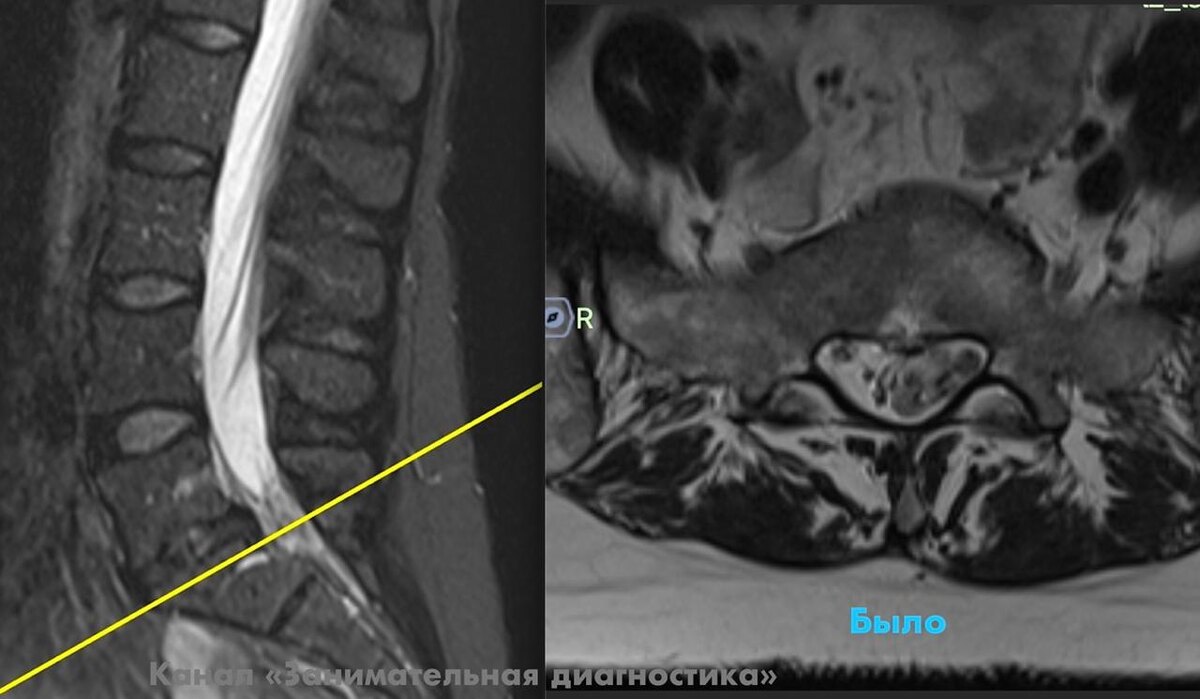

«У меня для вас две новости: плохая и хорошая», — сообщаю я пациентке.

«Плохая — у вас большая секвестрированная грыжа, которая защемляет корешки.

Пациентка очень обрадовалась и решила пока не делать операцию — до этого один врач настаивал на хирургическом вмешательстве, второй советовал подождать, и она не знала, как поступить.

Спустя 4 месяца на контрольном МРТ ожидания оправдались: грыжевой секвестр уменьшился в несколько раз, самочувствие пациентки заметно улучшилось, а «прострелы» по ноге ушли.